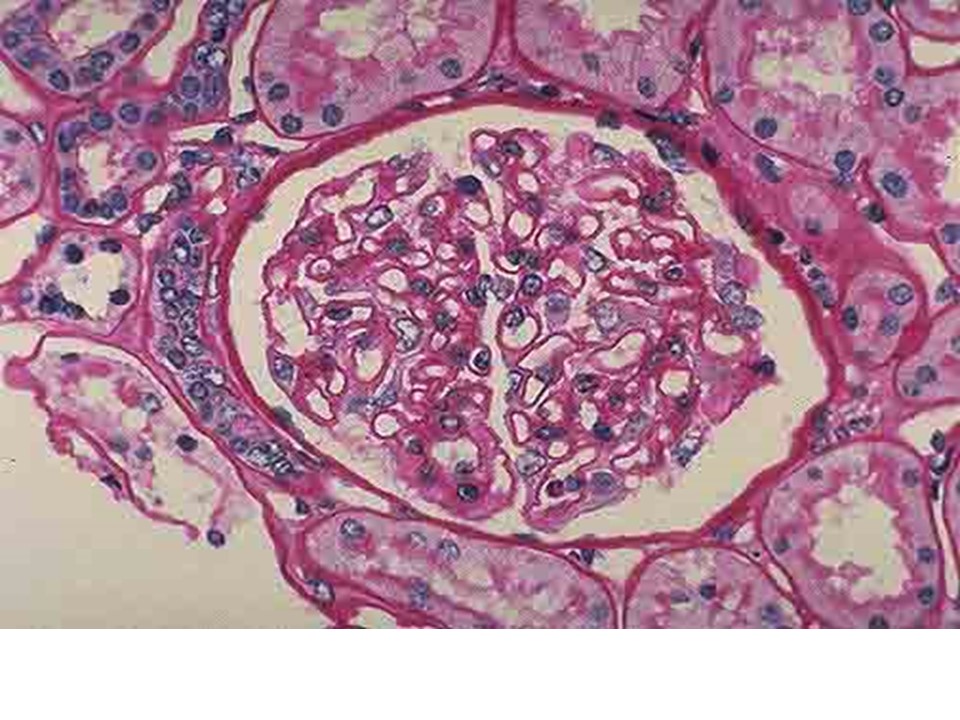

肾内科入科须知PPT

肾内科入科须知PPT遵守工作纪律,不迟到不早退。保持和谐的医患关系。与病人及家属充分交流,使病人了解诊断、治疗情况和预后。按照肾内科诊疗常规要求进行各种操作和特殊用药前的谈话,记录和术前准备。...